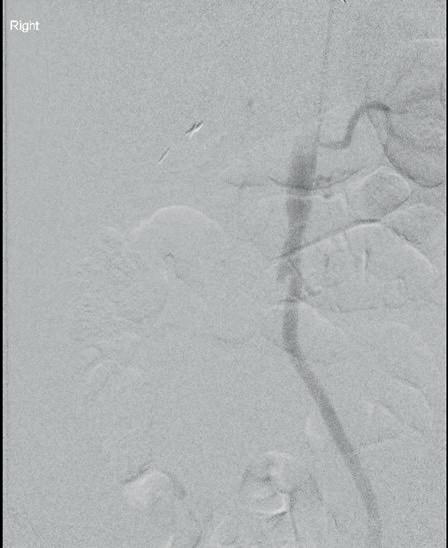

The study was a retrospective review of 66 patients with a median age of 31 who underwent UAE for uncontrolled postpartum haemorrhage at a single, high-volume medical centre between 2014–2022. UAE successfully controlled postpartum haemorrhaging in 62 of the 66 patients (94%). Four patients required hysterectomies to stop the bleeding, all of whom lost at least 2,400ml blood prior to presentation for UAE and showed symptoms of diffuse intravascular coagulopathy, a clotting abnormality that can happen after large-volume haemorrhage due to rapid consumption of clotting factors.

Postpartum haemorrhage is a rare, but potentially deadly complication of childbirth. To stop it, obstetricians will initially use conservative approaches to replace the lost blood or to promote clotting. If these measures are insufficient, hysterectomy is usually performed. Alternatively, interventional radiologists can be brought in to perform UAE, injecting tiny particles into the arteries that supply blood to the uterus using fluoroscopic imaging guidance. Once placed in the arteries, the particles temporarily block blood flow to stem uterine bleeding.

“Based on these findings, we would encourage obstetricians to involve interventional radiologists early, to be ready to perform UAE if more conservative approaches are not managing

postpartum haemorrhage,” said senior author James Morrison (Michigan State University, East Lansing, USA).